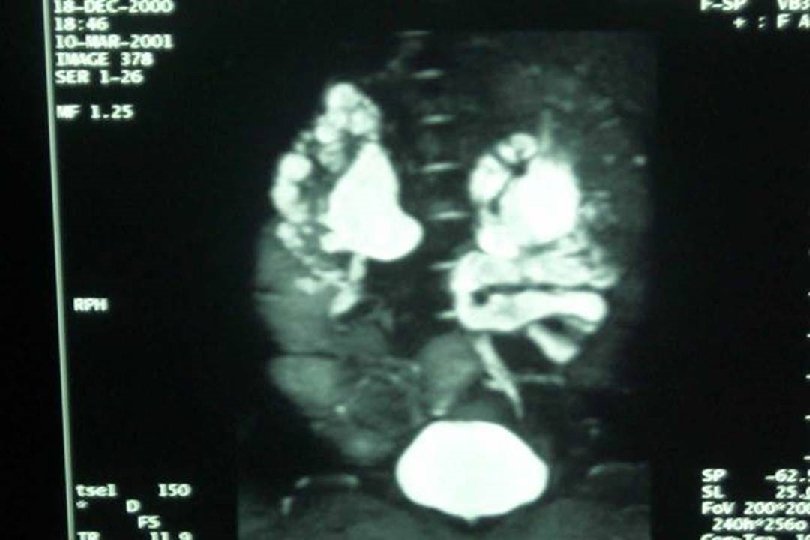

SECUENCIA DE IMAGEN o ECOGRAFIA. o CISTOURETROGRAFIA RETROGADA POST MICCIONAL. o PIELOGRAFIA ENDOVENOSA o GAMMAGRAFIA RENAL CON DMSA-TC 99. o RADIORENOGRAMA o UROGRAFIA POR RMN o TAC HELICOIDAL o ENDOSCOPIA VIRTUAL